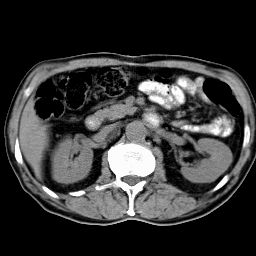

Это конфигурация для работы с изображениями. На рисунке видны два главных окна системы: окно Управление (справа) и окно Изображения, с изображением среза, полученного на рентгеновском томографе. Как выйти из системы. Первый вариант: надо активизировать в верхнем меню элемент CT, появится вертикальное подменю, и щелкнуть мышью на элементе Выход. Второй вариант: в латинском нижнем режиме клавиатуры (для активизации латинского регистра надо одновременно нажать клавиши Control-Shift, для активизации русского регистра - клавиши Alt-Shift - зеленая рамка по периметру экрана - признак русского регистра) нажмите клавишу x. После выполненных действий в любом варианте появится окно подтверждения выхода. Если вы не передумали выйти из системы щелкните мышью на кнопке Да окна подтверждения или при работе с клавиатуры: переведите курсор на кнопку Да и нажмите клавишу Enter. ГЛАВА 1. Работа с изображениями. Какие окна выведены на экран после входа в систему. Это окна конфигурации для работы с изображениями. Они перечислены ниже. Первые три окна присутствуют всегда.. Четвертое окно FG-сервис выводится, если в вашей системе есть оборудование для ввода видеосигнала

Для решения данных проблем разработана следующая схема передачи данных из ультразвуковой медицинской диагностической установки в персональный компьютер. (плакат 1) Я осуществлял подключение ультразвуковой диагностической установки ALOCA SSD 650. Она осуществляет срез информации органов исследуемого пациента на глубину до 30 см. от места контакта с телом пациента и работает на частоте от 2 до 7,5 мГц. И выводит информацию на экран с разрешением 640 * 480 с 64 уровнями градации серого. Полученная информация преобразуется в стандартный видеосигнал, который может быть снят с специализированных выходов. Захват и обработку информации из ультразвуковой медицинской установки осуществляется устройством, называющимся frame grabber. Оно позволяет в «реальном времени» преобразовать видеосигнал в цифровое изображение и сохранить его в персональном компьютере. К frame grabber’у предъявляется ряд характерных требований. Это должно быть устройство, позволяющее длительную оцифровку видеосигнала в реальном времени, обладать высокоскоростной «шиной», для быстрой передачи полученной информации в персональной компьютер. В нем должна быть предусмотрена возможность настройки яркости и контрастности для первоначальной настройки при подключении к медицинской диагностической установке и оно должно быть совместимо со всеми основными современными операционными системами. Всем этим требованиям удовлетворяет frame grabber HI*DEF PLUS фирмы IMAGRAPH. Данный frame grabber позволяет получать 256 уровней градации серого, что позволяет иметь запас по разрешению изображения для ультразвуковых медицинских установок более высокого класса и получать изображения, над которыми можно производить определенные операции. Кроме того, это сравнительно недорогое устройство, в своем классе, что является преимуществом, т.к. наши медицинские учреждения финансируются не достаточно. Frame grabber передает информацию в передает информацию в персональный компьютер первичного пользователя. Оптимальной конфигурацией персонального компьютера первичного пользователя является P2 – 400, 128, 4.3 + 18 SCSI, 8 V I740. Данная конфигурация предоставляет возможность осуществлять захват изображения из ультразвуковой медицинской диагностической установки, поддерживать режим телеконференций, осуществлять передачу получаемого сигнала по сети в реальном времени и обрабатывать получаемую информацию. Но т.к. парк персональных компьютеров в медицинских учреждениях России, на данное время, состоит из персональных компьютеров устаревших моделей, то в этом случае можно использовать лишь основные функции - захват и обработку изображений. Это можно осуществлять на персональных компьютерах класса DX4 – 100 с 16 мБ оперативной памяти, размером жесткого диска 800 мБ и сетевой картой NE2000 или совместимой. Персональный компьютер первичного пользователя позволяет передавать полученную информацию по компьютерной сети. Вопросы передачи информации по компьютерной сети подробно рассматриваются в дипломном проекте Еремеева Артема, который также выполнял дипломную работу в рамках проекта «телемедицина». К персональному компьютеру вторичного пользователя предъявляются те же требования, что и к персональному компьютеру первичного пользователя, за исключением того, что у в нем не устанавливается frame grabber для захвата изображения с ультразвуковой медицинской диагностической установки. В результате захвата изображения получается файл в котором необходимо отобразить не только информацию собственно о картинке, но и дополнительную. Для этого был разработан формат файла плакат 2 , который содержит в себе следующие поля: